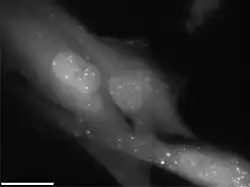

| Radiation causes cellular degradation by autophagy | |